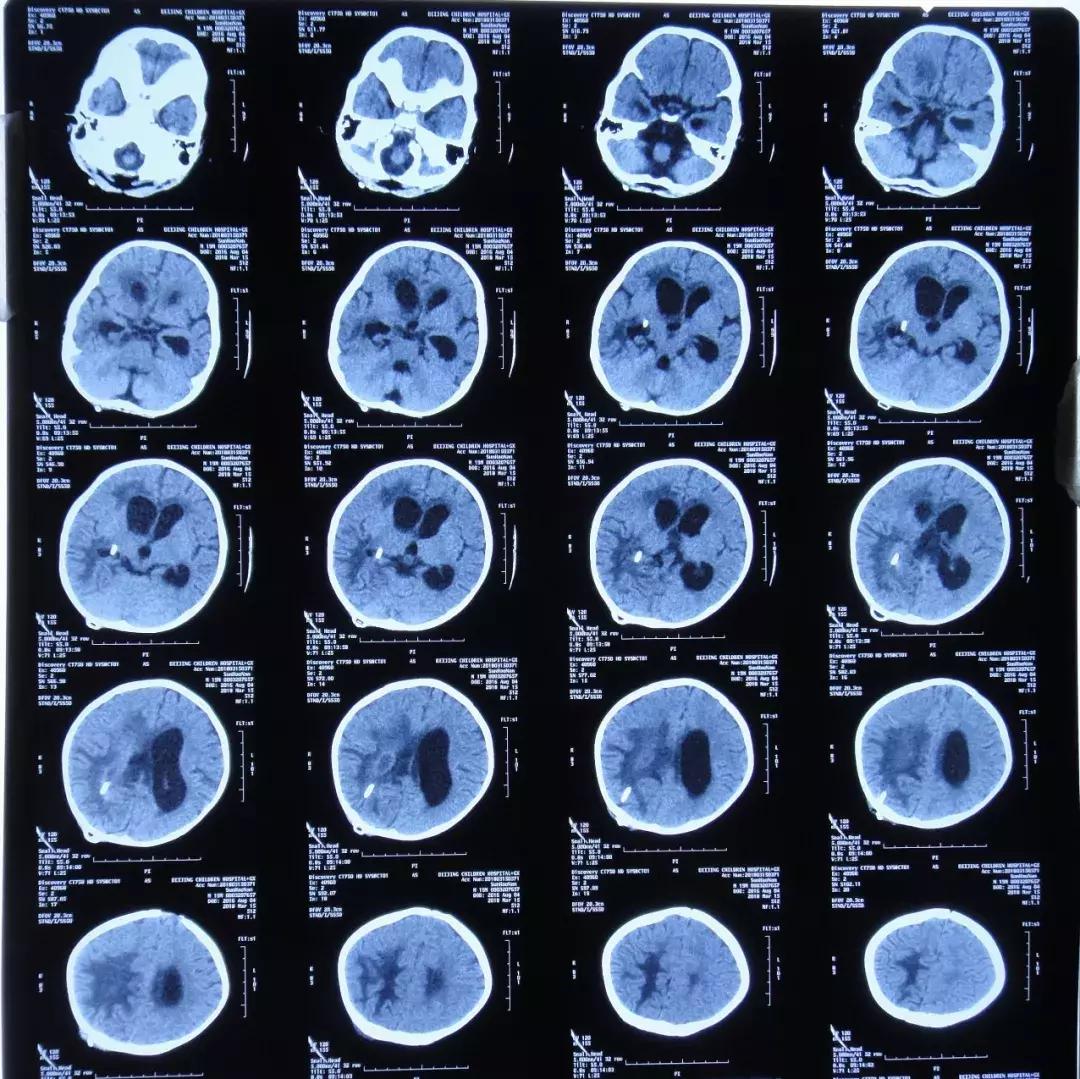

2018年3月14日头CT:脑室系统扩张 伴脑室旁水肿

2018年3月16日复查头CT:脑室系统扩张明显

3月14日,复查头CT:脑室系统扩张,伴脑室旁水肿, 3月15日再次加用两性霉素B,3月16日患儿呕吐明显,复查头CT:脑室系统扩张明显,当天晚上接受了经右额侧脑室穿刺Ommaya囊植入术,持续引*脑流**脊液,每日经右侧侧脑室腹壁外引流管引流量约60-80ml,Ommaya囊每日穿刺引流30ml,但是效果不佳,患儿仍有发热,呕吐等症状。为了寻求进一步治疗患儿转入李小勇脑脊液科。